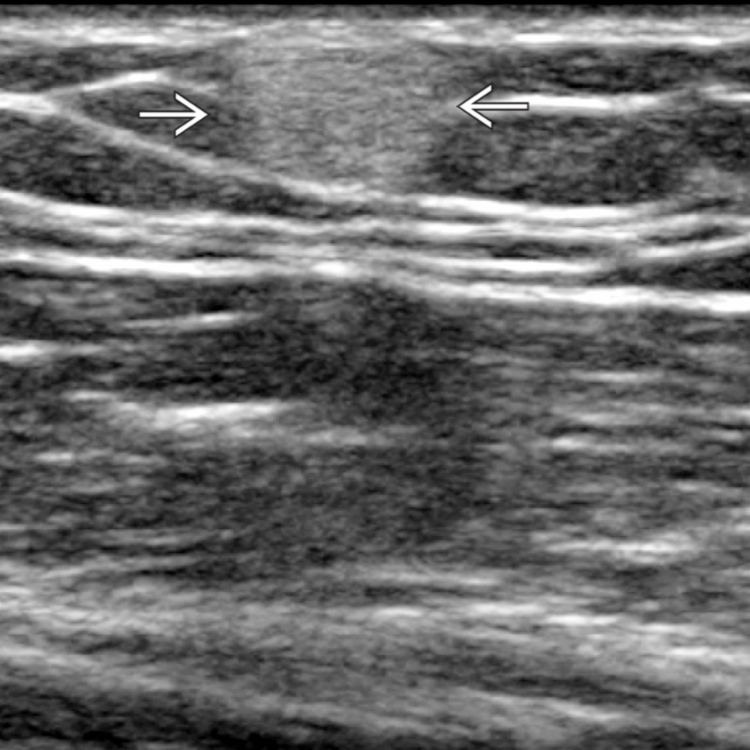

Lipoma of the spermatic cord. (a) US image demonstrates an echogenic …

Liposarcoma – on ultrasound | Image | Radiopaedia.org

Lipoma – subdeltoid | Image | Radiopaedia.org